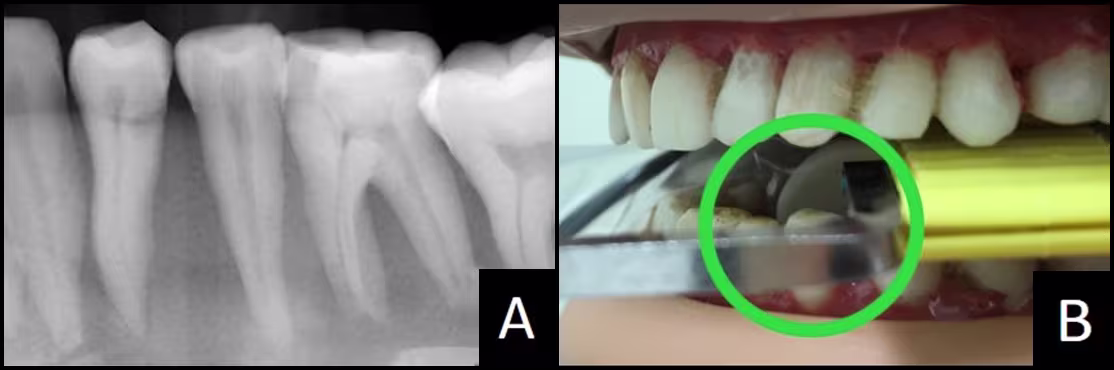

You must identify the correct horizontal angulation, and when standing in that path, make sure the active part of the sensor is physically within the radiation’s path. In Figure 9B, the photograph was created when standing in the correct horizontal angulation to capture the distal canine crown and to open the contacts around the first premolar. We can see active sensor positioned behind the canine #22 (within the green circle). The distal half of canine #22 and the premolars appear in the periapical image. In Figure 10, canine #22 does not appear in the image. Looking through the aiming ring, we see the sensor’s dead zone behind the canine. This can be difficult to correct. Keep reading and find solutions in Problem #3.

Figure 9 - Premolar Periapical

(A) Image with required distal crown #22.

(B) Verification of active sensor behind #22 within green circle.